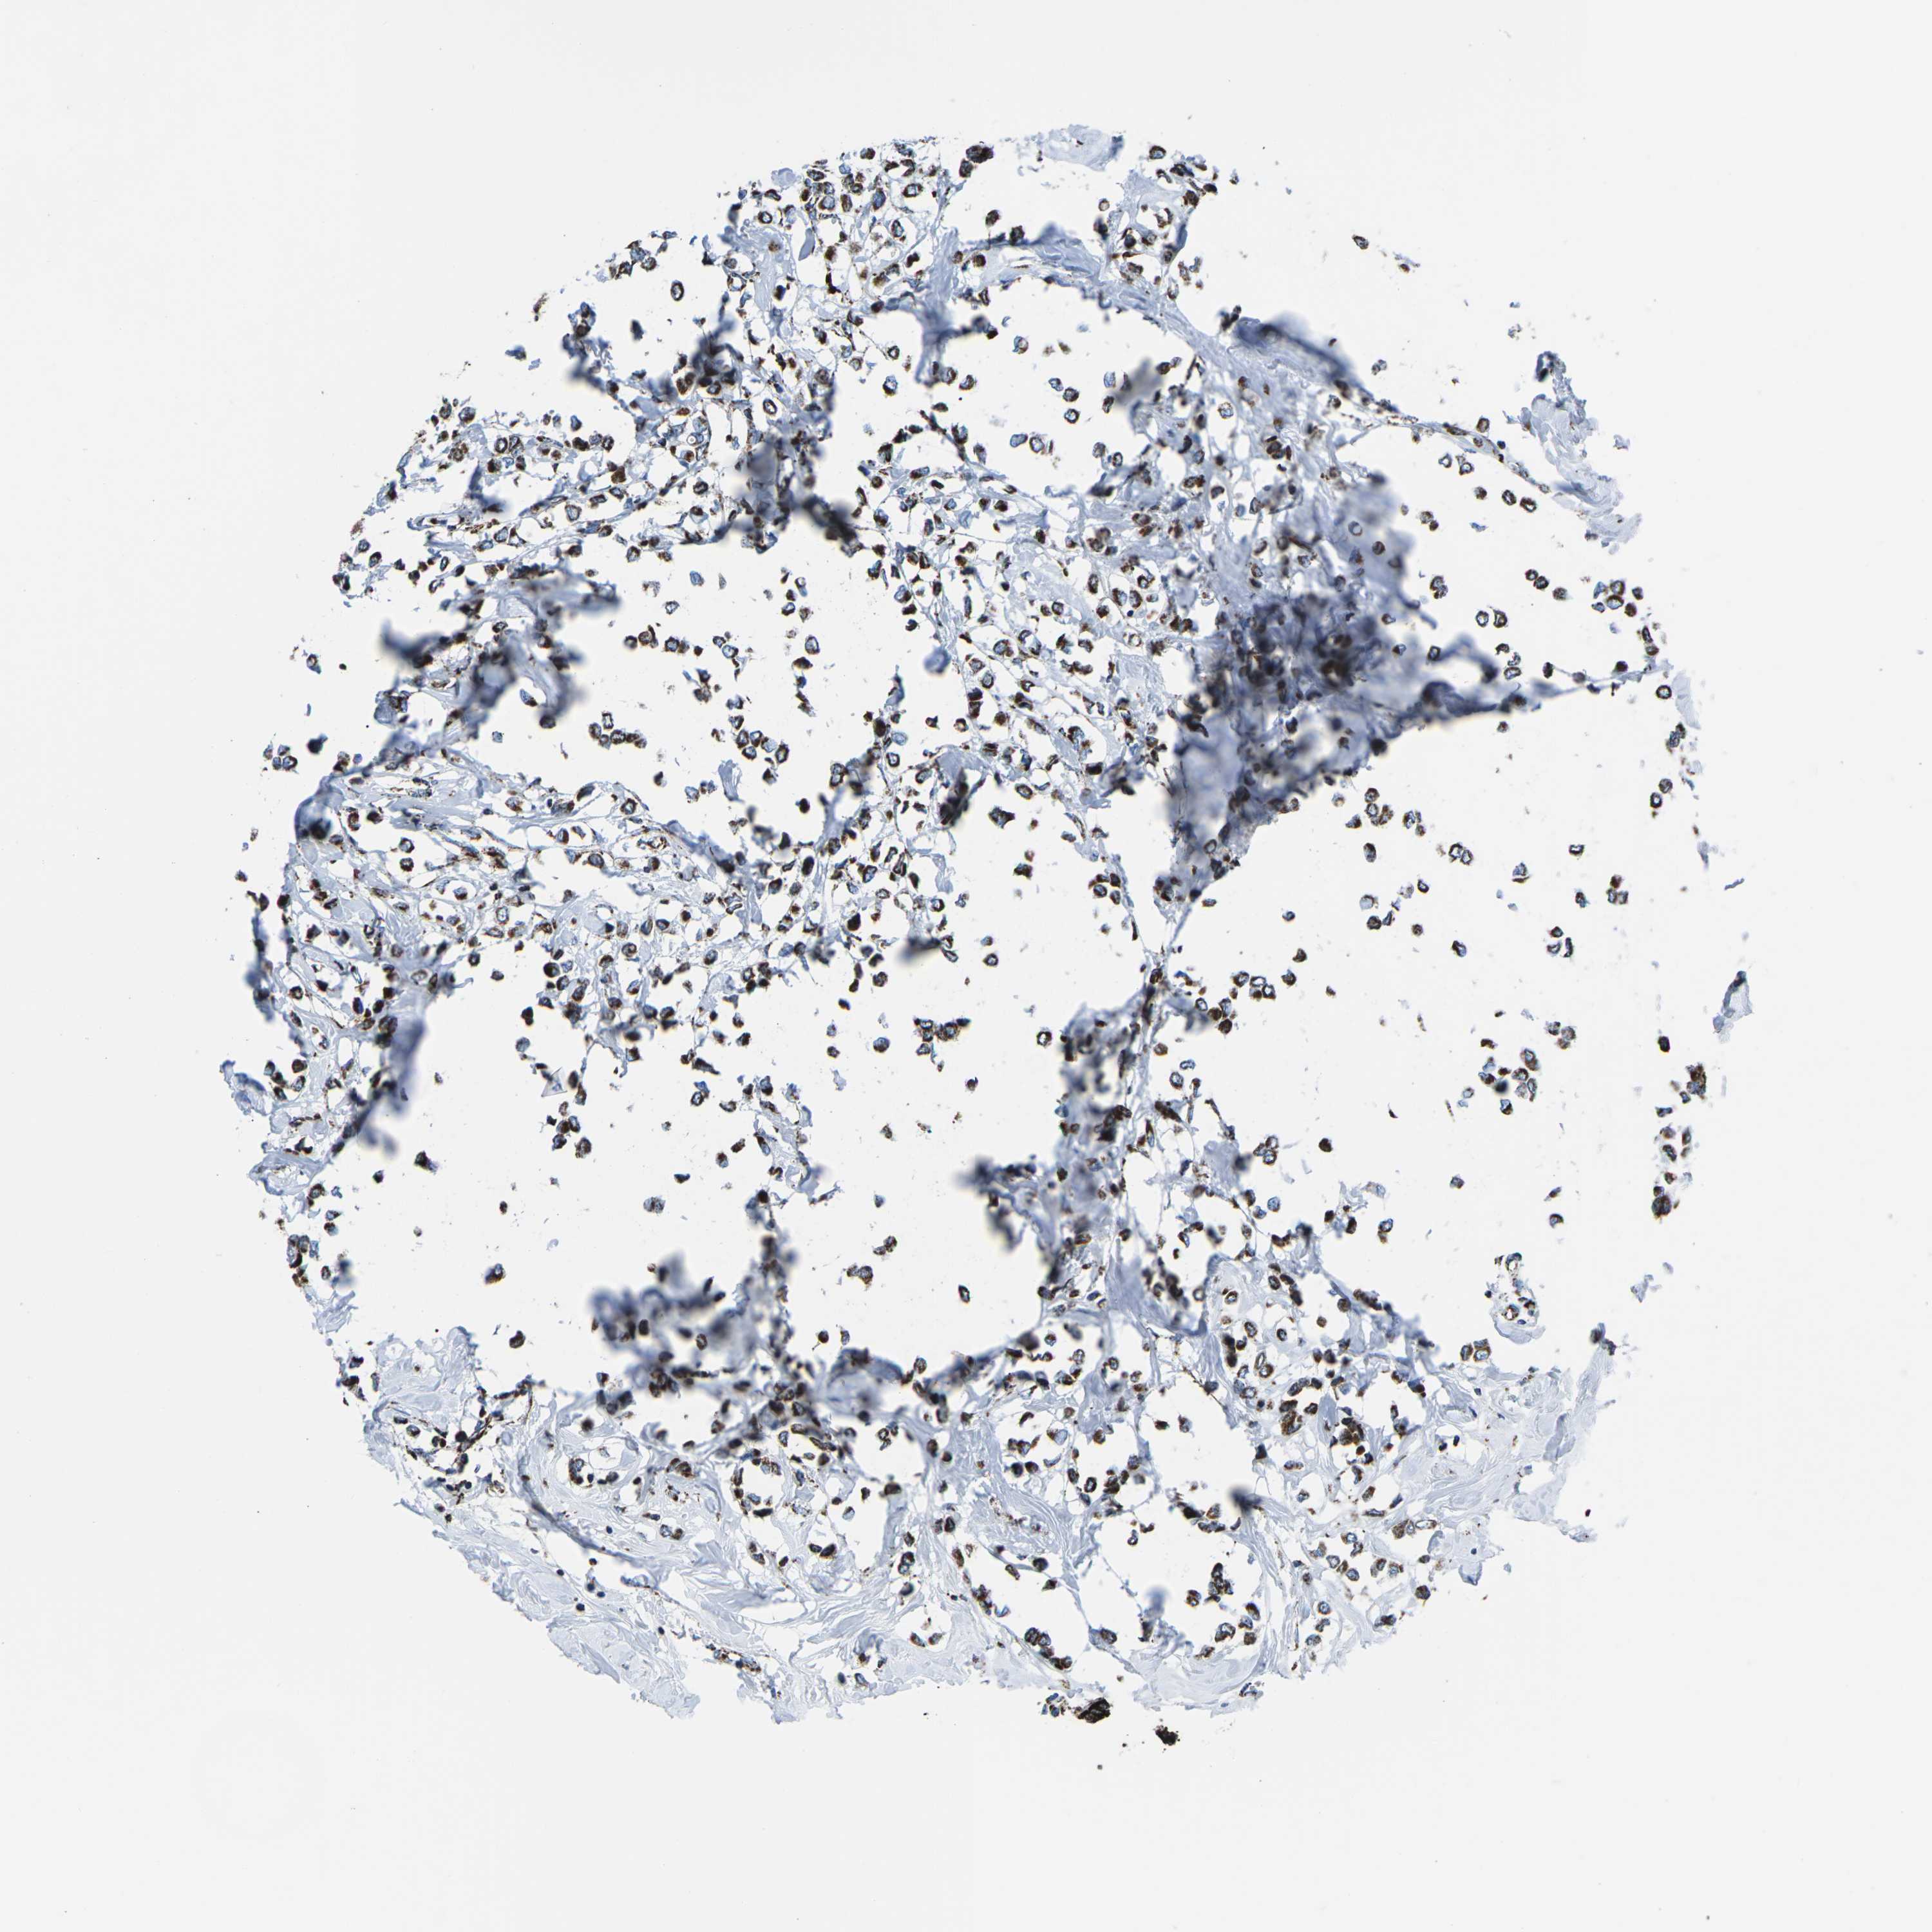

CANCER BREAST CANCER Show tissue menu

BRCA TCGA BRCA VALIDATION PROTEIN EXPRESSION

ANTIBODIES

AND

VALIDATION